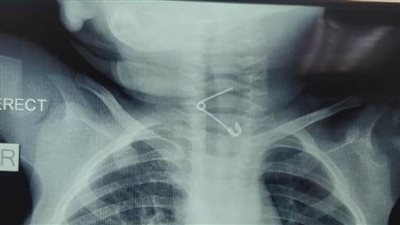

إنقاذ حياة طفل ابتلع مسمار دباسة بمستشفى الأطفال التخصصي في بنها